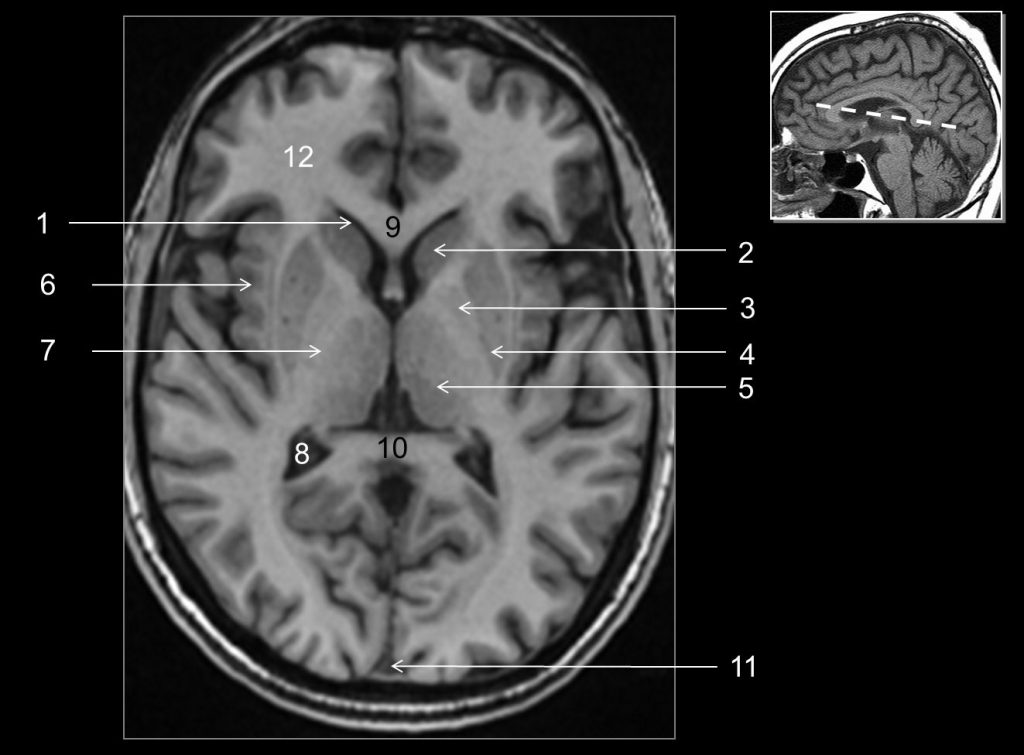

Fig. 48.5 Coupe axiale (IRM) en pondération T1.

1. Tractus optique. 2. Corps mamillaire. 3. Pédoncule cérébral. 4. Aqueduc du mésencéphale. 5. Vermis. 6. Hémisphère cérébelleux. 7. Hippocampe du lobe temporal. 8. Cortex insulaire. 9. Lobe frontal.

Source : CERF, CNEBMN, 2022.